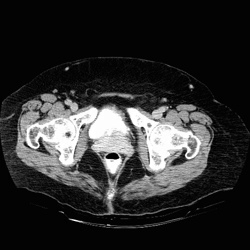

RADIOLOGY: GENITOURINARY: GU: Case# 33015: URETHRAL CA. 61-year-old female. Mass lesion which lies in the expected area of the urethra. It is difficult to determine vaginal extension for reasons noted above.